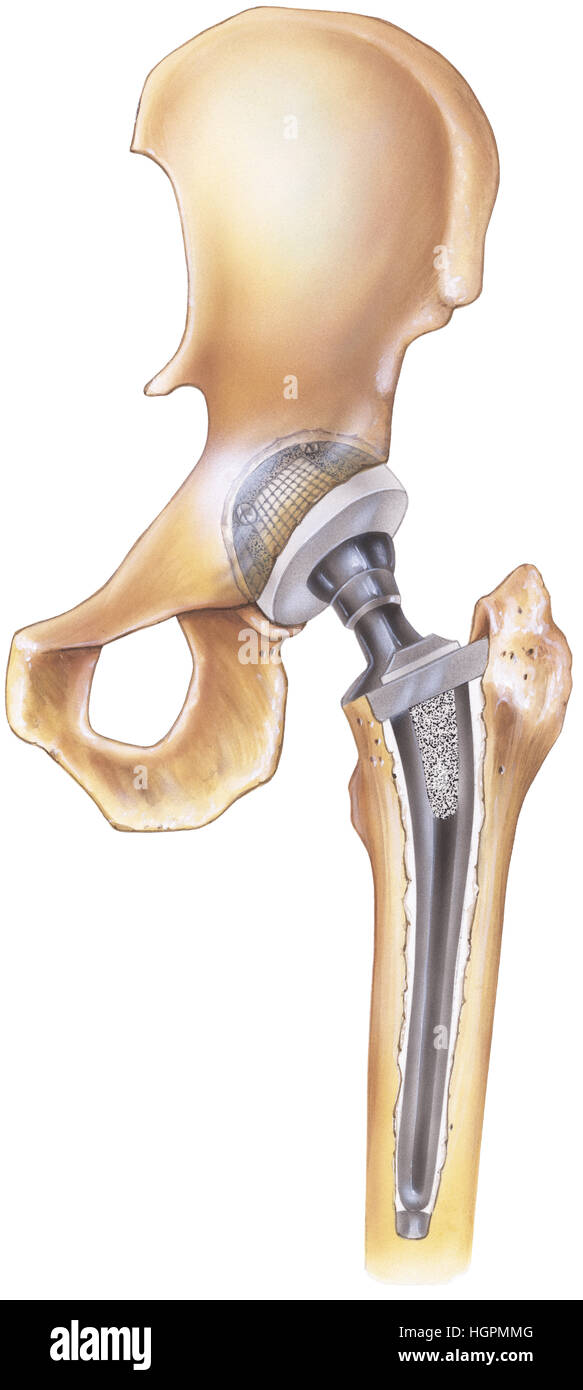

Замена таз сустава

Замена таз сустава 113 фотографий